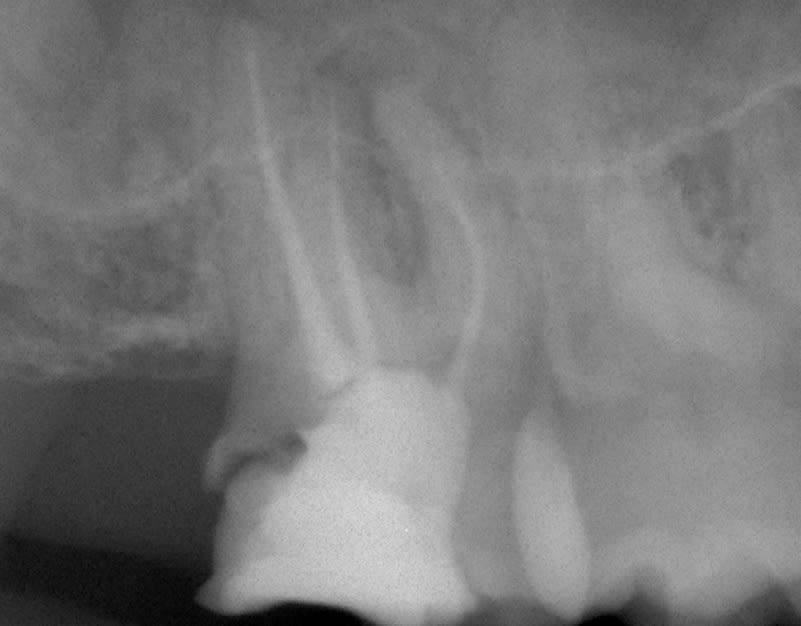

Bon petit cas de ce matin. Reprise de traitement endo sur 17, Préparation coronoradiculaire infragingivale.

Retraction gingivale et empeinte optique. Bonne lisibilité des limites dans l'empreinte optique mais j'ai fais un silicone pour tester la fonction qui a très bien marché.

On s'éclate! https://www.meditlink.com/webViewer?shareKey=f58f58e8-4d35-4a29-b8f8-82b6dccf92b7

Sinon Kingsu, superbe ton sauvetage de 17.